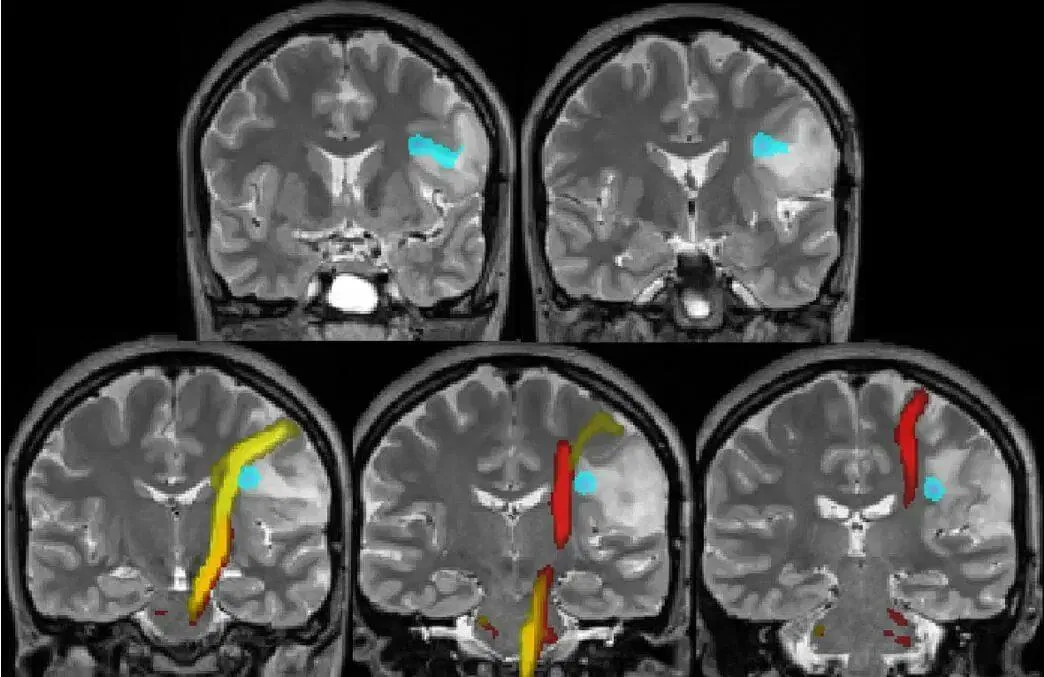

There are well-established fMRI studies showing that when we read narrative stories, the brain partially activates the same regions that would be active if we were physically or emotionally experiencing what the character experiences.

example of fMRI imaging

In other words, our brains are imitating what the character in the story goes through. Regions involved in vision, hearing, bodily sensation, movement, and emotion all show activity during story-reading. This doesn’t mean the brain can’t tell fiction from reality, it means stories work through simulation rather than conscious instruction.